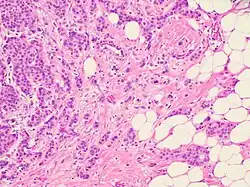

Histopathologic criteria

On microscopic evaluation carcinomatous cells are seen below the basement membrane of lactiferous ducts and invade into the surrounding breast stroma. Otherwise, there are no specific histologic characteristics, essentially making it a diagnosis of exclusion.[21] The histopathologic characteristics seen in these lesions are heterogenous. The cells of a lesion of invasive carcinoma NST may retain >70% ductal differentiation or appear completely undifferentiated. The tumor cells may be arranged in sheets, nests, cords, or singly distributed. They are pleomorphic (i.e., vary in size and shape). They usually have prominent nucleoli and multiple mitotic cells per magnified field of view, which are features generally consistent with cancerous cells. The surrounding non-ductal tissue, known as stroma, can range from none to abundant.[22][23]

Small inclusions of special features may be present within an invasive carcinoma NST tissue sample, but will be 'limited' (i.e. <10%). Carcinomas of mixed type will have a specialized pattern or lobular carcinoma in the majority (i.e. at least 50%) of the tumor and a non-specialized pattern in between 10 and 49% of the sample. Thus, such tumors will be called mixed invasive NST and special type or mixed invasive carcinoma NST and lobular carcinoma.[24]

Histopathology of invasive ductal carcinoma of the breast representing a scirrhous growth. Core needle biopsy. Hematoxylin and eosin stain.

Invasive ductal carcinoma of the breast. H&E stain.